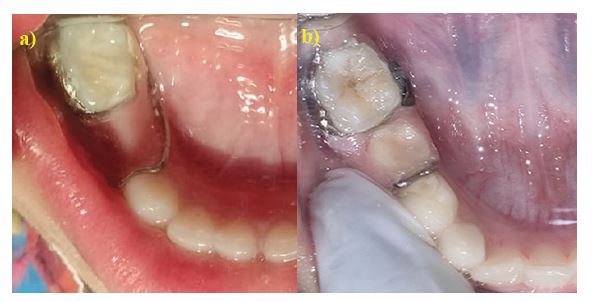

Group 1: Conventional band and loop (CB&L) space maintainer (Figure 1a)

Group 2: Fixed functional band and loop (FB&L) space maintainer (Figure 1b)